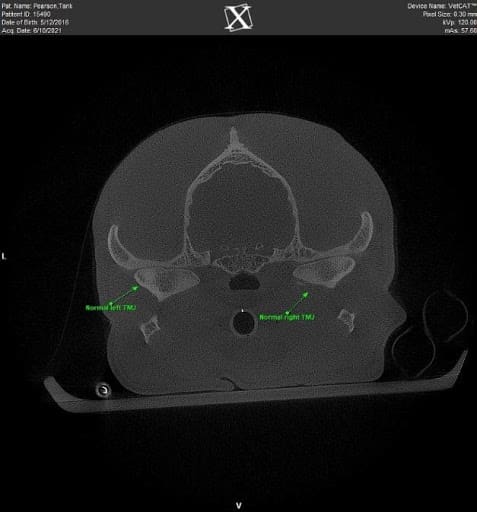

Figure 1 Cone Beam Computed Tomography image of normal TMJs in an adult dog

Anatomically, the condylar process of each mandible articulates with the mandibular fossa of the temporal bone. A fibrocartilaginous disc provides a cushion at the joint surfaces. The TMJ in dogs plays a role in occlusion (or the way teeth meet) and is prone to developmental, traumatic, and age-related diseases.

TMJ disease is diagnosed most accurately through imaging. Skull radiographs are beneficial but often are challenging to interpret as they are two-dimensional images. Cone-beam CT imaging provides 3-D evaluation and is invaluable for diagnosing TMJ disorders. This imaging modality is completed under general anesthesia, with imaging results in less than 4 minutes in most patients.